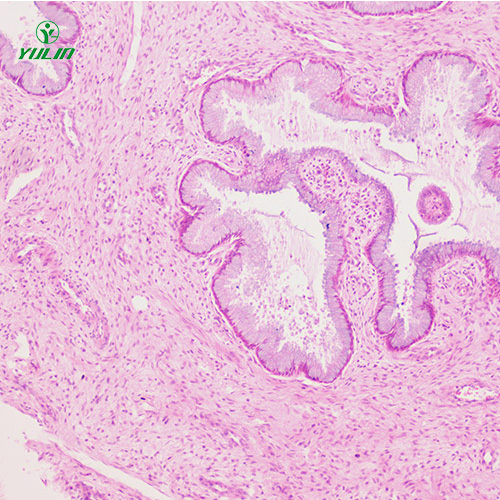

众所周知,人泌尿生殖系统疾病标本片需要在浙江显微镜下观察,但是很多用户不知道如何更好的使用人泌尿生殖系统疾病标本片。所以给大家讲解一下如何使用人泌尿生殖系统疾病标本片。

3.观察:将需要观察的人泌尿生殖系统疾病标本片放在托盘上,用夹子夹住,并确保人泌尿生殖系统疾病标本片正对着通光孔的中心。然后转动粗准焦螺旋,使镜筒慢慢下降,直到物镜接近生物显微玻璃片,左眼向目镜内看,同时逆时针转动粗准焦螺旋,使镜筒慢慢上升,直到看到物体图像。

说到人泌尿生殖系统疾病标本片,我们都会想到实验课上做的一些实验。我们都知道人泌尿生殖系统疾病标本片可以帮助我们更好地学习生物。然而,在制作人泌尿生殖系统疾病标本片的过程中,不可避免地会出现一些问题。这里了解一下制作过程中会遇到哪些问题。

1.采样的优缺点:样品的优缺点会直接影响人泌尿生殖系统疾病标本片的制作。在采样过程中,建议大家准备一把锐利的采样刀,避免采样时拖延,采样时尽量按照与化纤平行面切除。

2.固定后的水清洗:很多用户在制作人泌尿生殖系统疾病标本片时,往往会忽略固定后的水清洗步骤或水清洗不好,导致托盘和着色不艳丽。

3.固定问题:这个过程主要是为了更好地避免细胞组织的自溶性腐烂和细胞内部酶对蛋白质的分解,从而维持与原始生活的结构。然而,许多实验者无法掌握这部分内容,这严重影响了人泌尿生殖系统疾病标本片的观察效果。

脱干:脱干不好是人泌尿生殖系统疾病标本片生产中导致生物结构不透明的主要因素,而脱干过多容易导致生物机构变脆。

上色不均匀或不正确:建议大家在给人泌尿生殖系统疾病标本片上色时,要根据染料的温度、切片类型、新旧来确定染色时间。